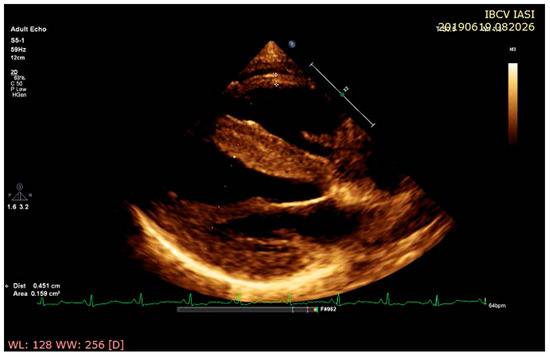

3. Advanced Echocardiographic Techniques

3.1. Advanced Echocardiographic Techniques in Amyloidosis

3.2. Advanced Echocardiographic Techniques in Sarcoidosis

3.3. Advanced Echocardiographic Techniques in Hemochromatosis